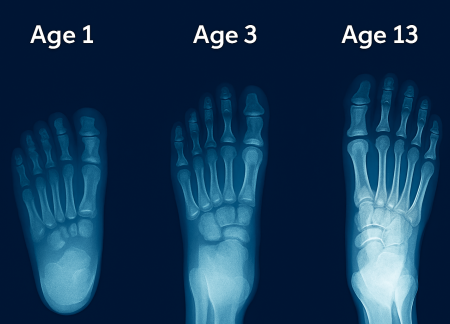

A newborn’s foot is deceptively complex. At birth, it contains all 26 bones that will eventually form the adult foot—but most exist as soft, pliable cartilage. These cartilaginous precursors are separated by wide growth plates (epiphyseal plates), allowing rapid expansion. The heel bone (calcaneus) and metatarsal heads are among the first to begin ossification, but the navicular bone—critical for arch formation—remains cartilaginous until age 3–5.

The foot appears flat, wide, and pudgy, with a thick fat pad concealing the underlying structure. This fat pad serves dual purposes: shock absorption during early weight-bearing and protection for delicate tissues. By age 2, this pad begins to thin, revealing the emerging arch.

Ossification is not linear—it accelerates during growth spurts:

| Age | Key Ossification Events |

|---|---|

| 0–1 year | Calcaneus, talus, cuboid begin hardening |

| 2–3 years | Metatarsal heads ossify; fat pad thins |

| 4–6 years | Cuneiforms solidify; medial arch emerges |

| 8–10 years | Navicular fully ossifies; longitudinal arch matures |

| 12–14 years | Growth plates close; adult proportions achieved |

By age 13, the foot reaches 90–95% of adult length, but width and arch height continue refining until 16–18.